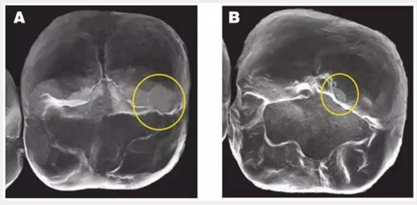

2. 牙冠對對頜牙造成的磨損:這三種冠材料與對頜牙的接觸中都會造成小的磨損平面(加下圖)BruxZir 的磨損平面更大也更多。這些修復(fù)體使用一年后出現(xiàn)的磨損平面,需要更多的時間去觀察。(見下圖)

圖像A和圖像B 顯示了Bruxzir和切削類e.maxCAD全冠對對頜牙造成的磨損平面。本次研究中所有的材料(包括控制對照組)都會一些造成類似的小磨損平面。無論對頜牙是釉質(zhì)、鑄造金屬、復(fù)合樹脂還是瓷。